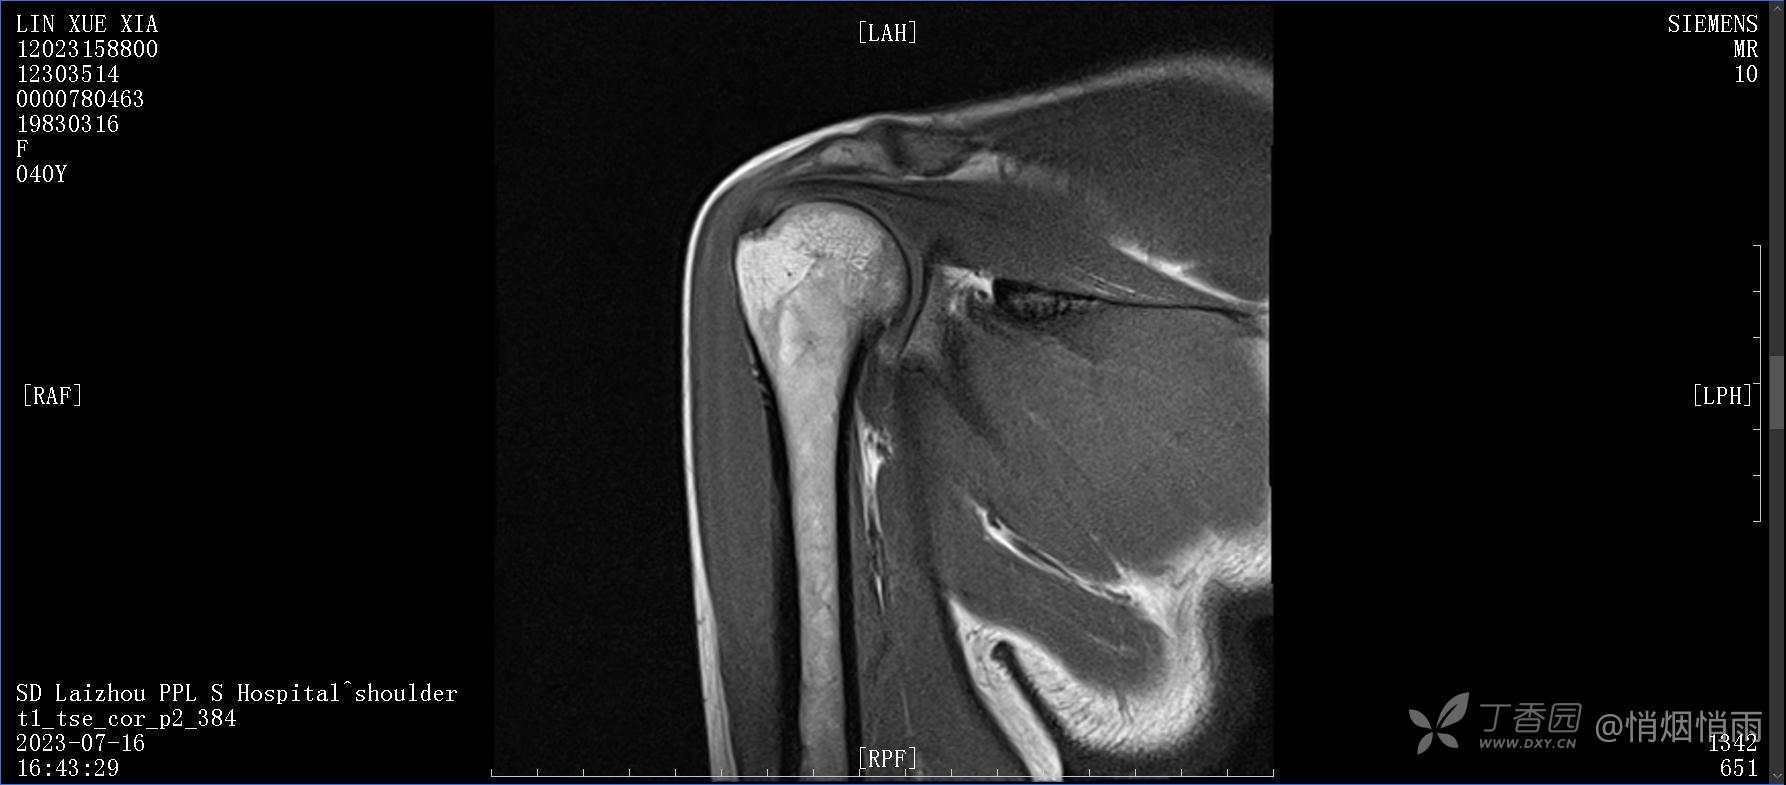

查体:右肩关节局部轻度肿胀,肩胛区压痛明显,痛处不固定,肩关节痛性活动受限,jobe test(+),lift -off test(+),中指、环指感觉较余指减退,余肢端感觉及血运情况可。

目前的诊断,暂时依据辅助检查诊为肩袖损伤,但是患者疼痛的性质和特点,却不是单纯的肩袖损伤所致。考虑过胸廓出口综合征,但是该疾病会出现肩胛区的疼痛吗?(由于考虑到费用的问题,没再进行下一步的检查)带状疱疹会有如此的症状吗?